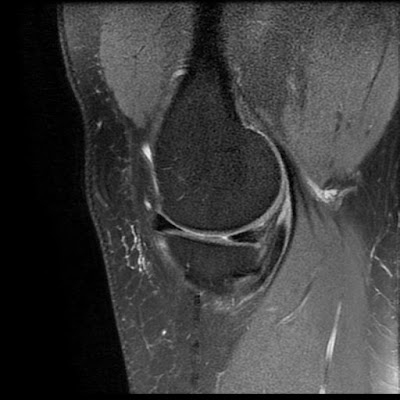

Parrot Beak Tear